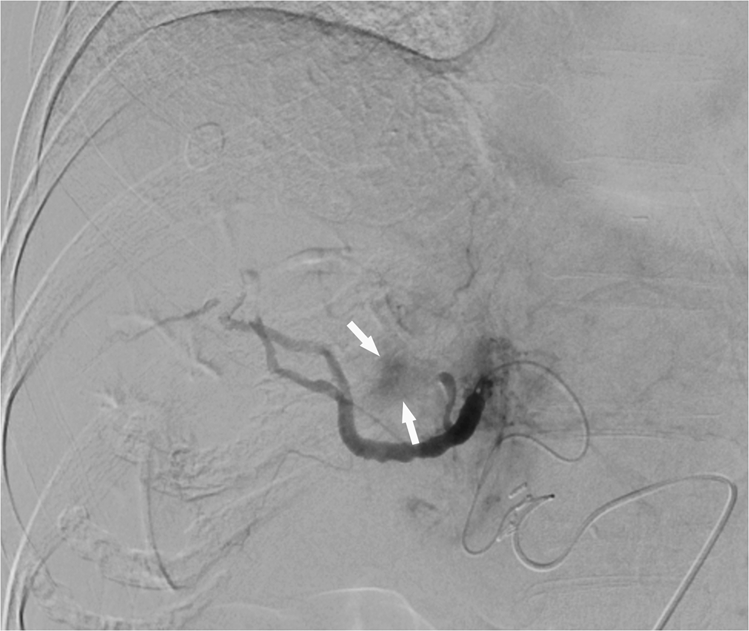

Figure 4

Post-TACE right hepatic angiogram showing residual tumor blush (white arrows) during arterial-phase imaging. It is a residual intratumoral enhancement on completion arteriography during TACE.